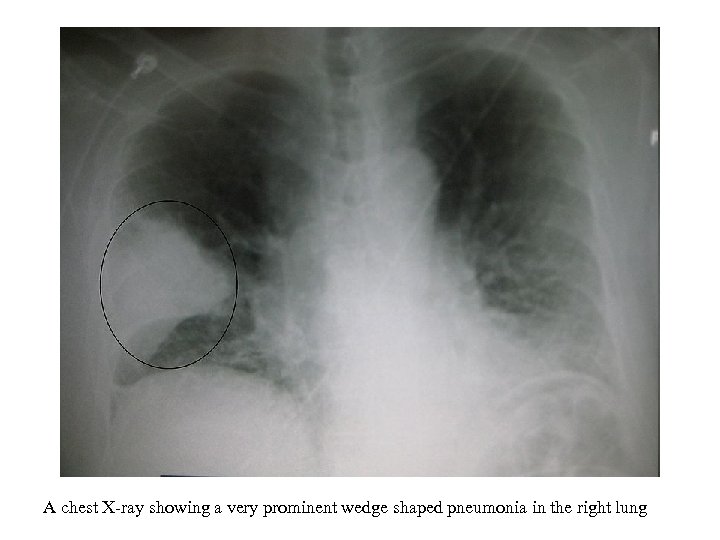

Lat CXR: RLL pneumonia